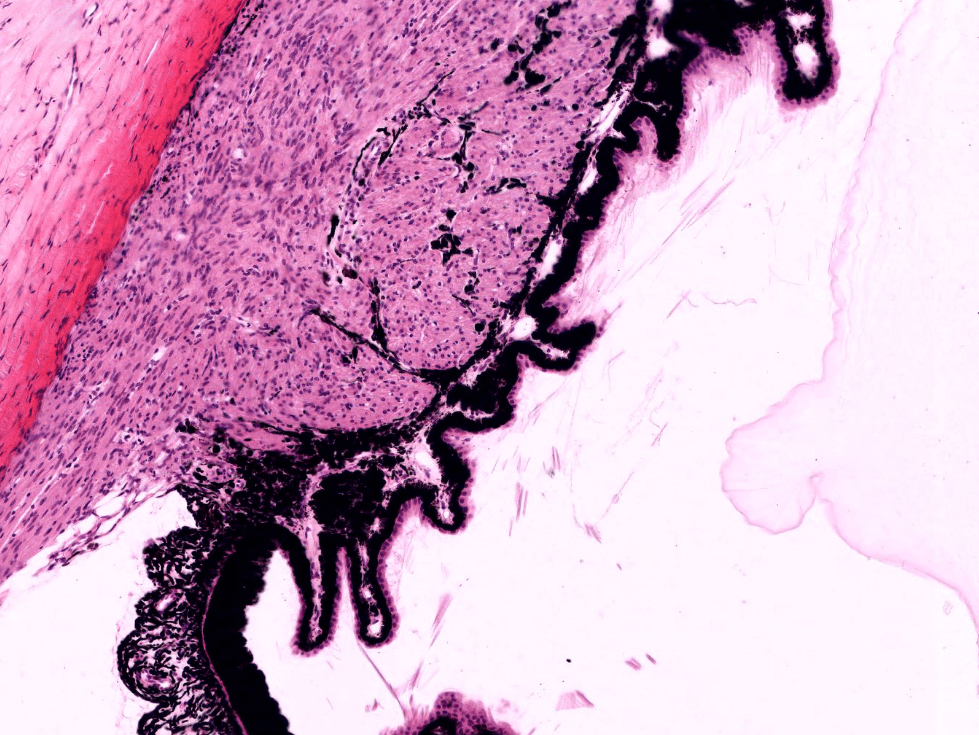

CUERPO CILIAR